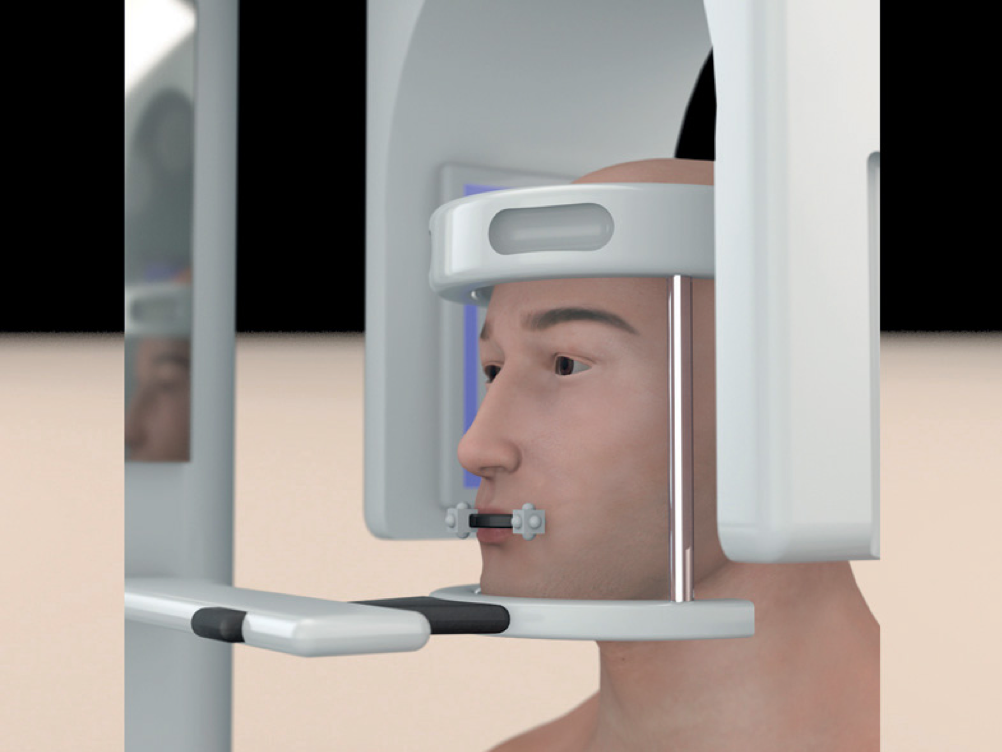

Quarta Fase

TAC con Universal Stent